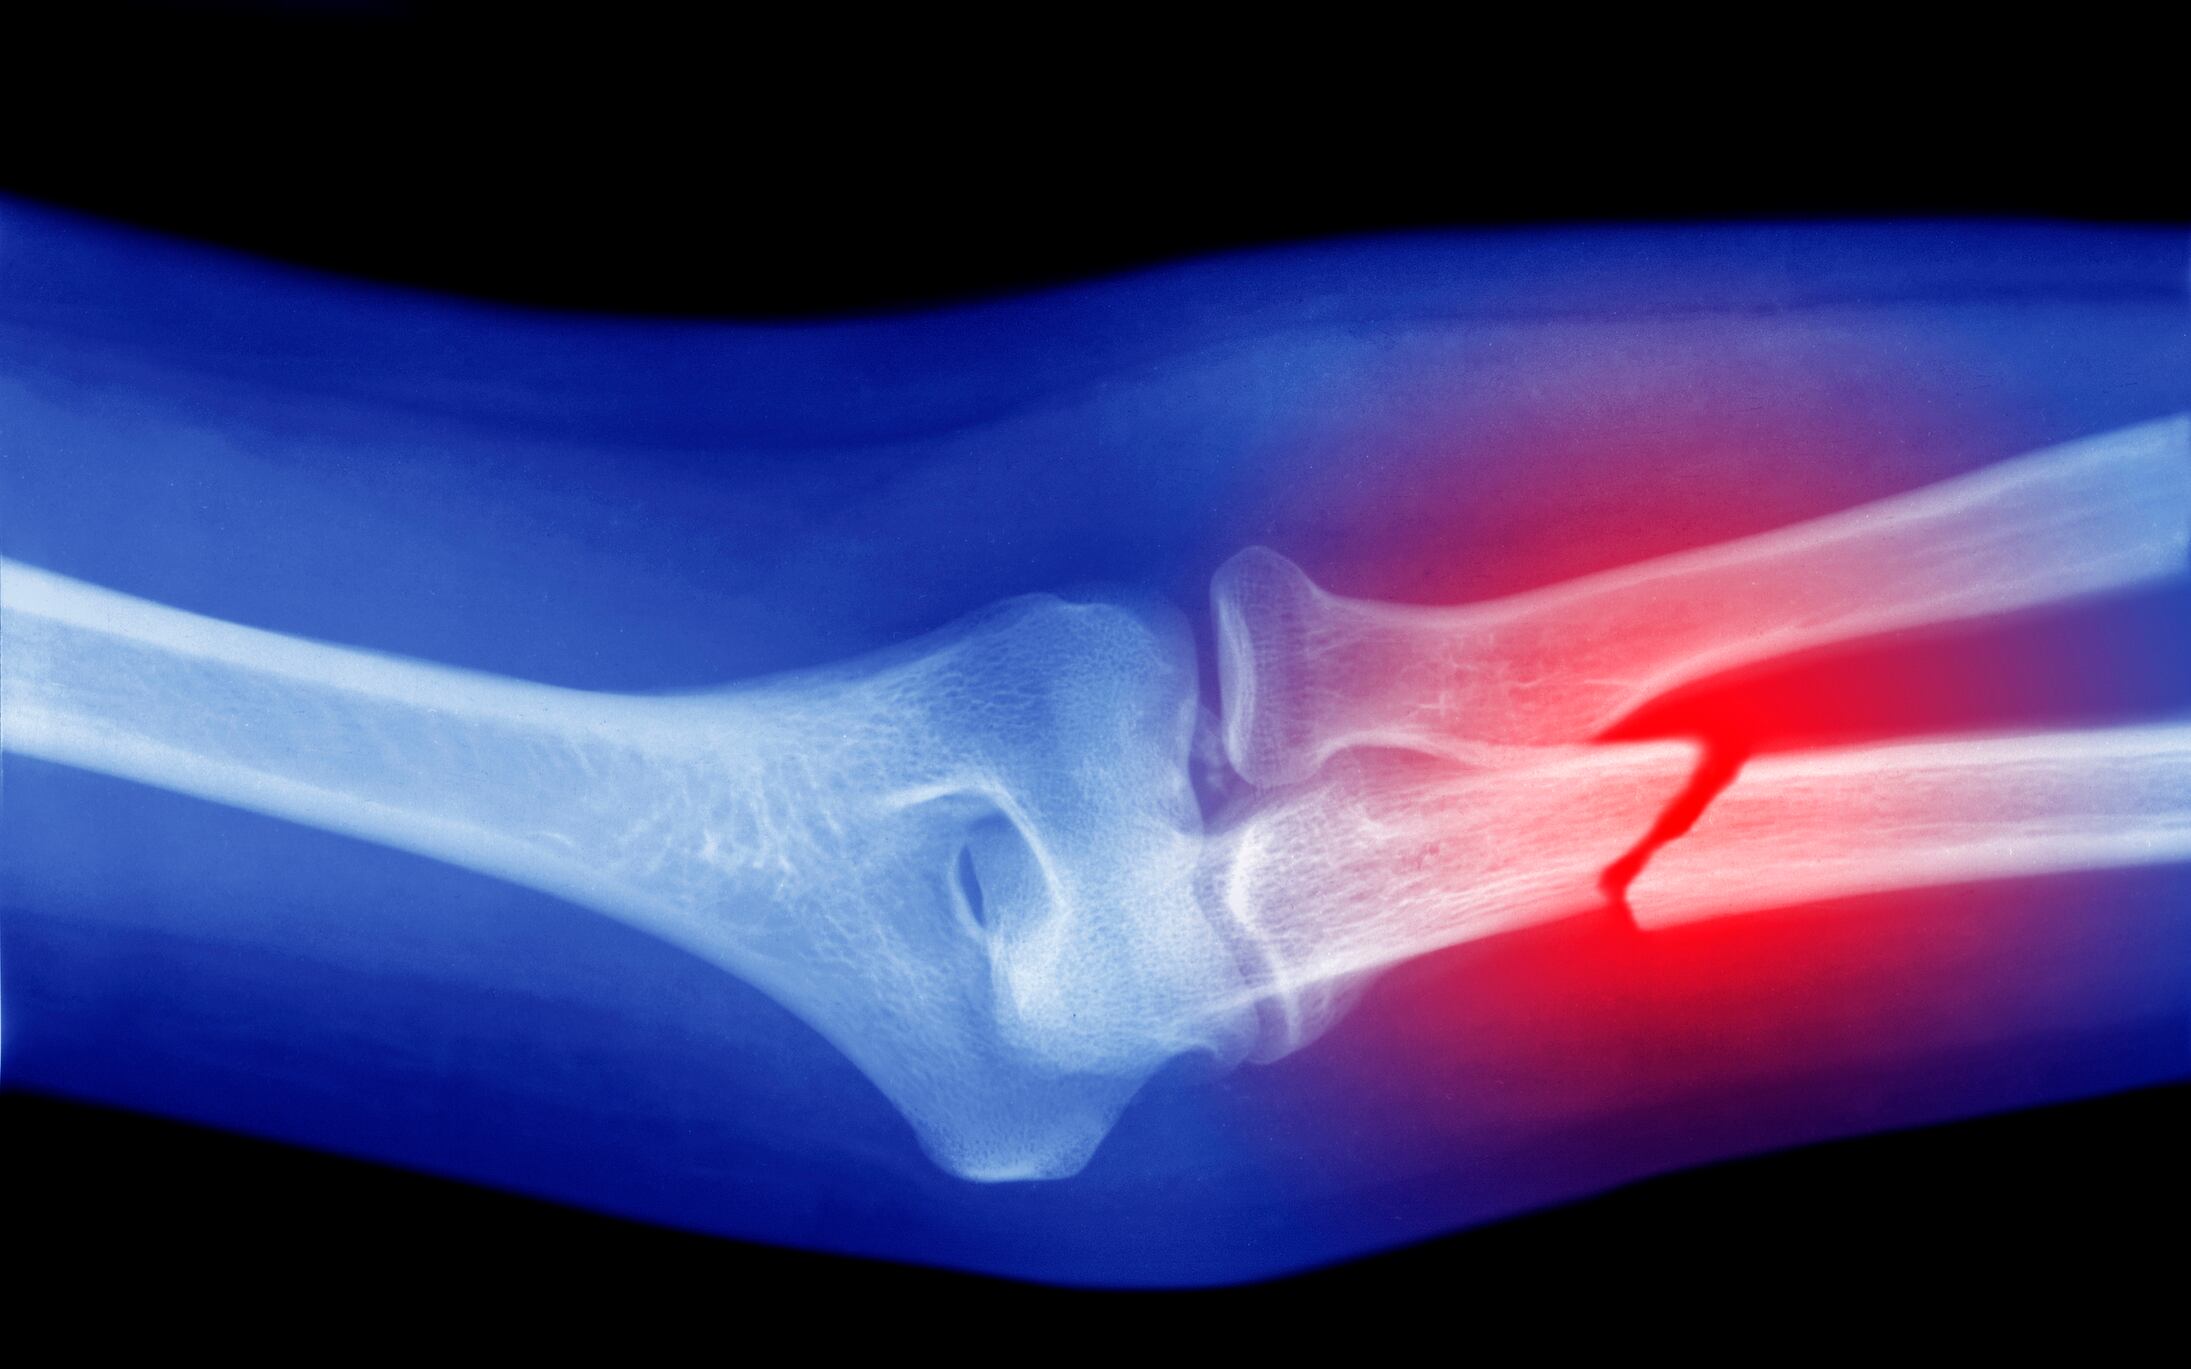

Hueso roto / Getty Images / Peter Dazeley